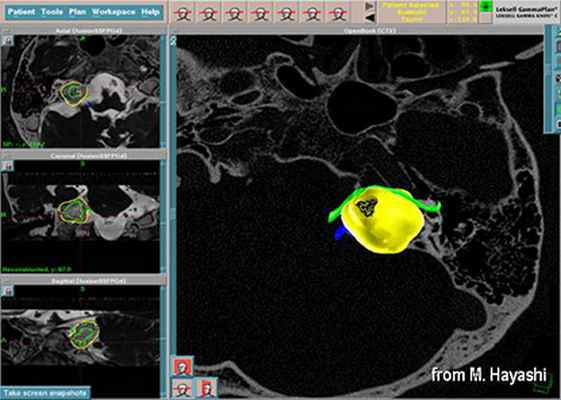

До начала радиохирургического лечения проводится обследование, позволяющее определить точное положение опухоли и прилегающих нервных образований. Выполняется трехмерная реконструкция, отображающая детальную микрохирургическую анатомию этой области. Для этой цели с помощью МРТ получают четкую визуализацию опухоли и нервов во внутреннем слуховом проходе и области мосто-мозжечкового угла.

С помощью планирующей системы Gamma Planи автоматической позиционирующей системывозможно проводить очень точное облучение опухоли (точность 0,5 мм), избегаяповреждения черепных нервов и других важных отделов мозга.

Преимуществами лечения на Гамма-ноже являются высокая степень сохранения функции лицевого нерва (в 98%) и слуха (в 80%). Полностью отсутствуют осложнения, связанные с открытой операцией (менингит, ликворея). Лечение проводится за один день. Госпитализации и послеоперационного восстановительного периода не требуется. Большинство пациентов возвращаются к своему обычному образу жизни на следующий деньпосле операции.